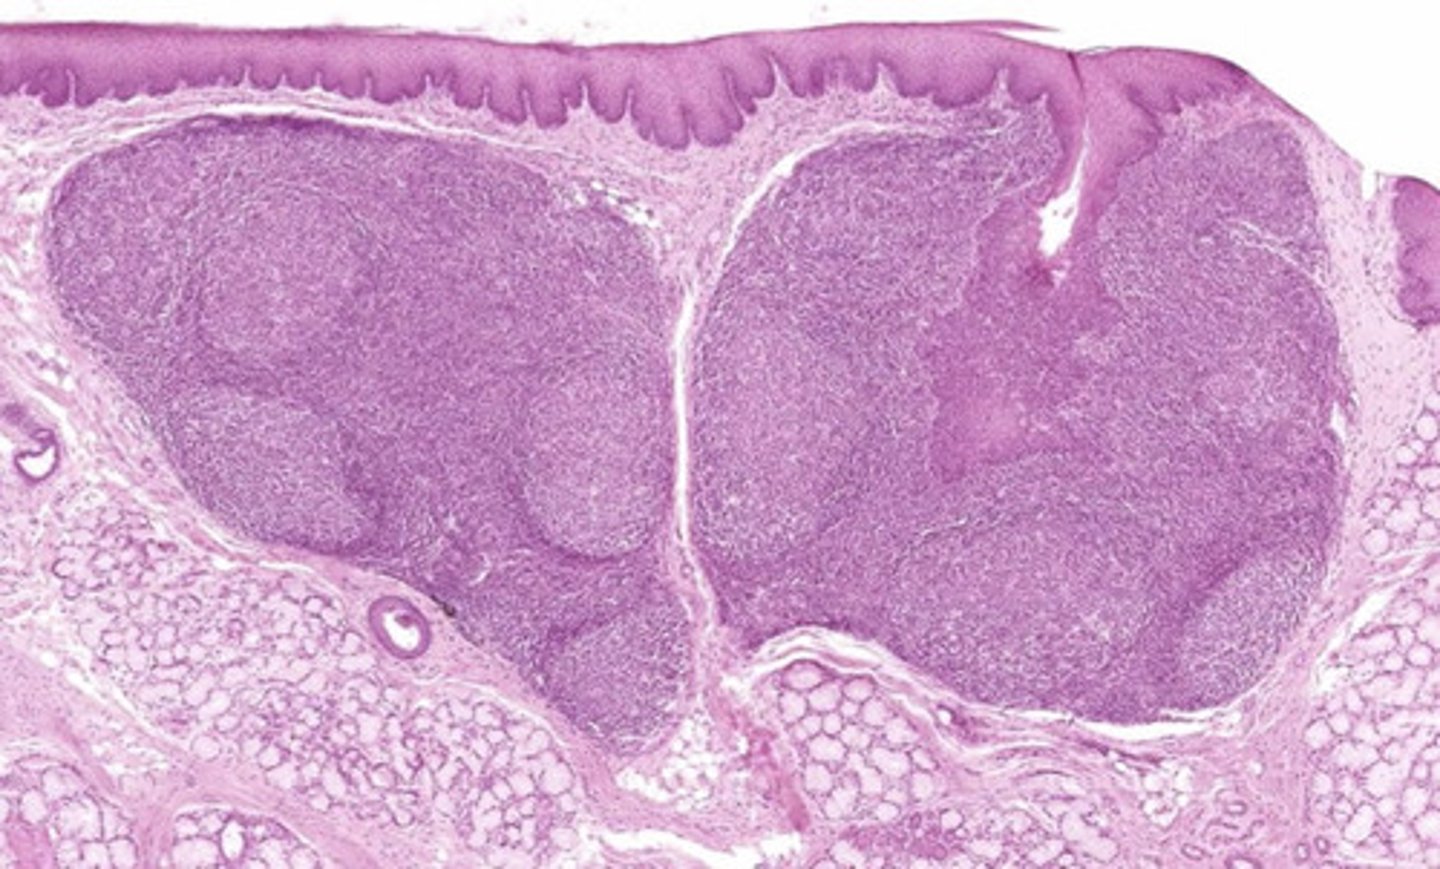

tonsil

what is this?